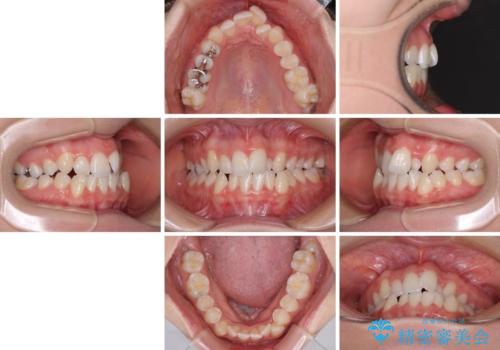

- 上下前歯のデコボコを気にして来院された患者様です。

上顎骨の横幅が狭く、奥歯は上顎よりも下顎が外側にある咬合状態でした。

歯列矯正では基本的に骨格を改善することはできませんが、急速拡大装置(MARPE)を使用することで上顎骨を側方に拡大させることができ、咬合状態を大きく改善することができます。

事前に急速拡大装置で側方拡大を行い、上下を目立たないワイヤー装置により歯列を整えていくこととしました。

急速拡大装置により骨格はある程度改善されましたが、奥歯の咬み合わせ改善に非常に時間がかかってしまいました。

デコボコを改善させるだけでなく、しっかりとした咬合状態を獲得することができ、患者様には大変満足していただけました。